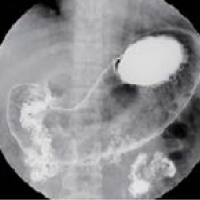

기초검사와 일반검사에서 얻은 자료를 토대로 각종 영상판독 소견을 종합하여 종합검진결과를 완성합니다. 검진결과를 참고하여 필요한 경우에는 개인맞춤 처방을 제공합니다. 또한 내과외래 진료도 진행하여 환자들의 내과진료를 담당합니다. 소화기 내과에서는 위/대장 내시경 검사 및 판독결과 상담을 통해 소화기질환 및 암검진에 대한 상담 및 처방을 진행합니다.